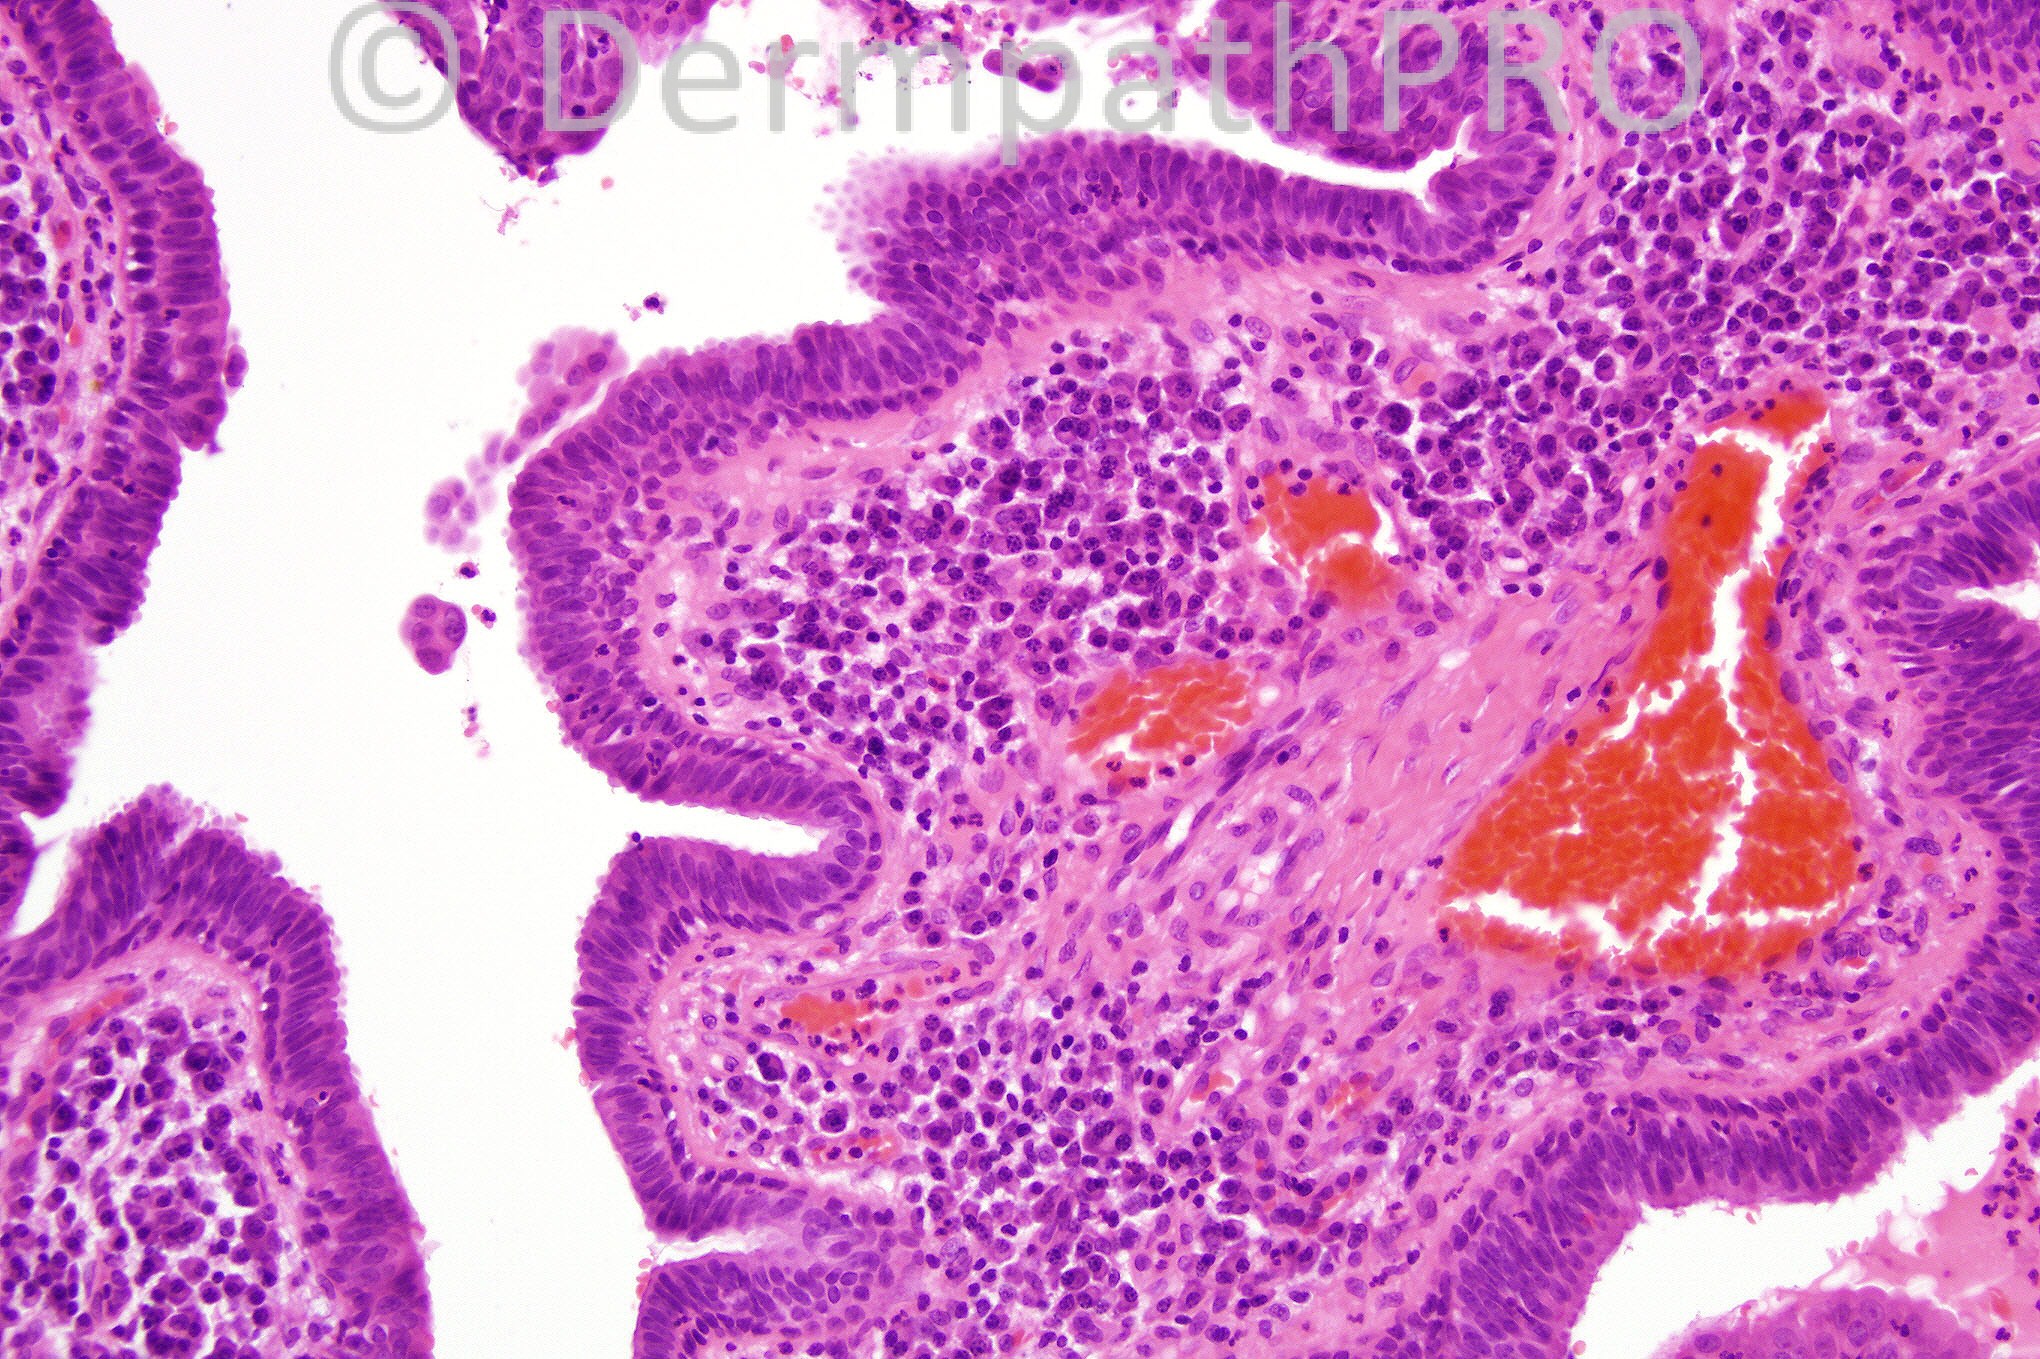

Male 49 years with a keratotic papule on the neck.